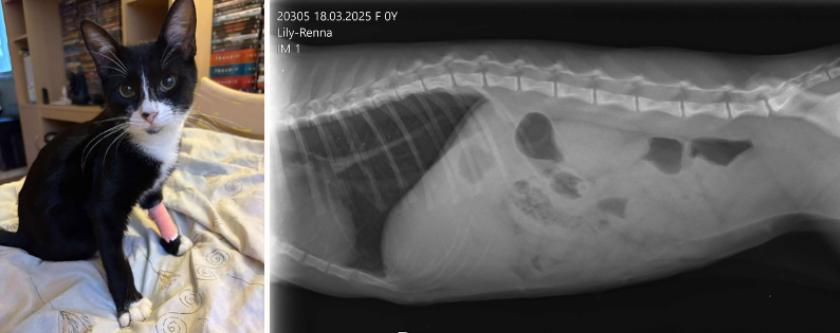

Meie poole pöörduti suure murega oma kuue kuuse kassi Lily-Renna pärast. Pererahvas märkas, et kassil algas ootamatu veritsus, mille käigus väljus ka tilluke kassiloote fraktsioon. Selgus, et Lily oli jäänud tiineks, kuid tiinus katkes. Omanikul kahjuks on hetkel väga rasked ajad ning ta oli meile helistades väga mures, sest teadis, et kass vajab kiiret abi, kuid rahaliselt polnud see tema jaoks võimalik.

Nii me otsustasimegi omapoolset abi pakkuda. Kliinikus selgus, et olukord on väga tõsine - Lilyl diagnoositi piometra ehk mädaemakas, mis on raske ja sageli eluohtlik põletik, kus emakas täitub mädase vedelikuga. Piometra põhjuseks on hormonaalsed muutused ja bakterite sattumine emakasse ning selle võivadki saada steriliseerimata kassid pärast jooksuaega, kui nende emakas on haigusele vastuvõtlikum.

Kuna mädaemaka diagnoos vajab kiiret sekkumist, sest ravimata jätmisel võib lõppeda sepsise ja looma surmaga, siis otsustati kassile teha kohe operatsioon. Protseduuri käigus eemaldati põletikus emakas koos sinna jäänud väljaarenemata lootekestadega. Operatsioon läks hästi ja Lily-Renna on nüüd steriliseeritud ning paraneb.